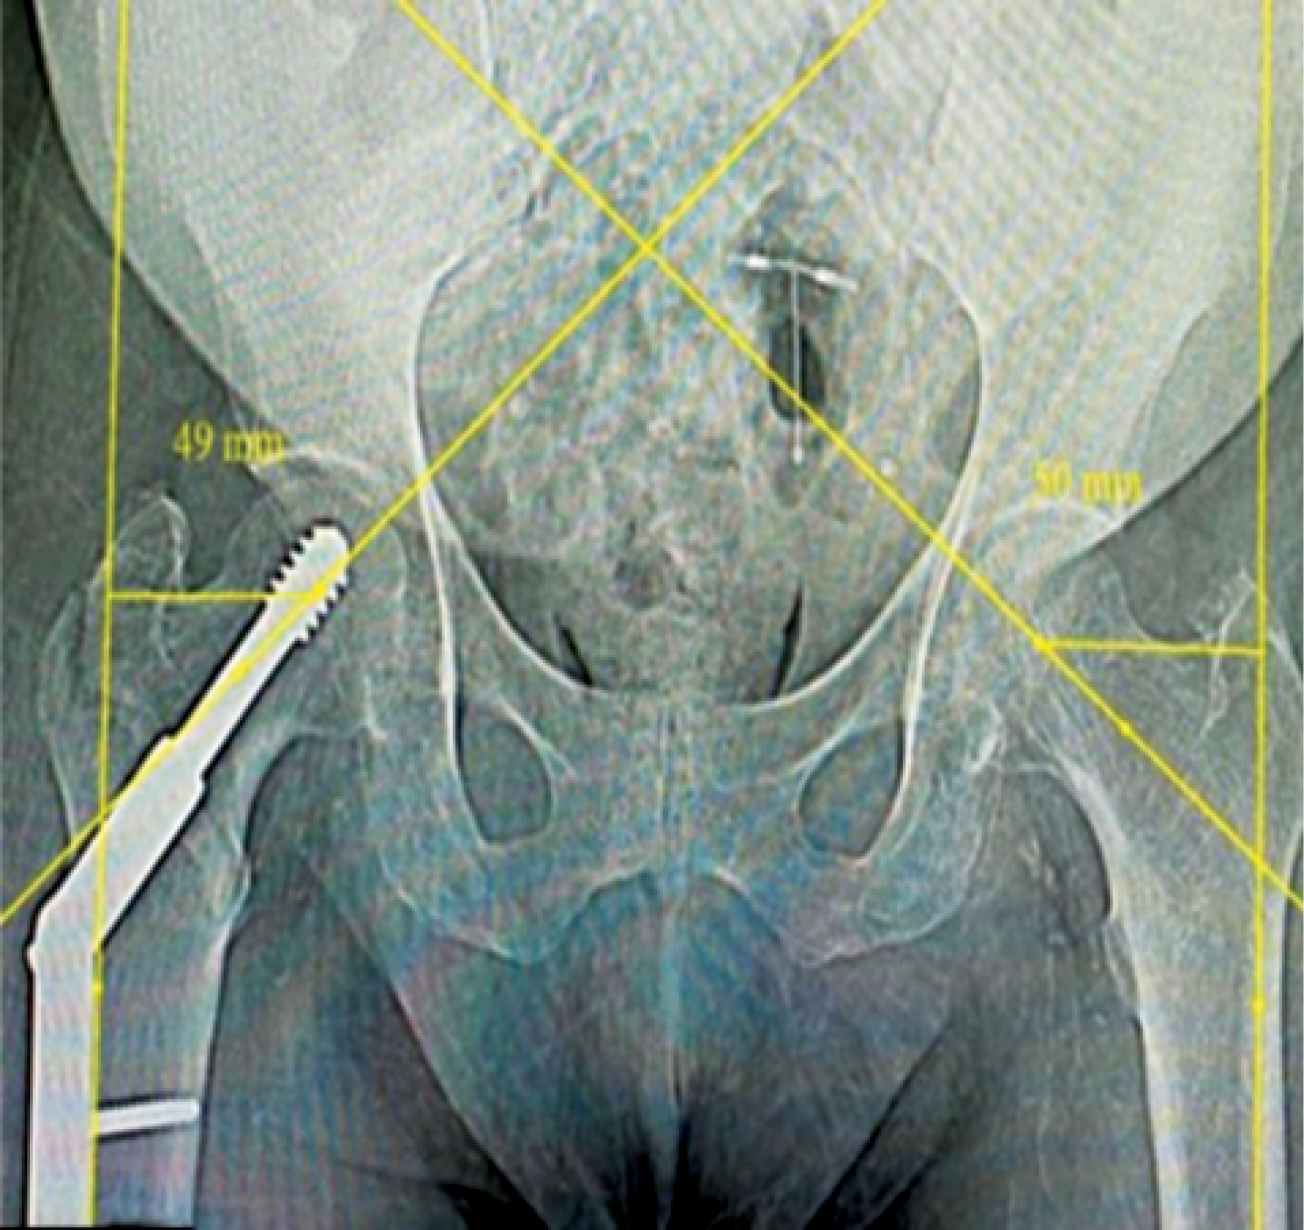

In the PFN group (n = 20), the mean lateralization of the FS on the injured side was statistically significantly higher compared to the DHS group (56.60±7.07 vs 49.50±6.59 mm; p = 0.002). However, on the non-injured side, there was no statistically significant difference between the PFN group and the DHS group (51.65±4. vs 49.65±6.09 mm; p-value = 0. 261) (Figures 5, 6, 7).

Figure 6. X-ray of a patient from the DHS group, showing femoral shaft lateralization (uninjured side — 50 mm, injured side — 49 mm)

Figure 7. X-ray of a patient from the PFN group, showing femoral shaft lateralization (uninjured side — 47 mm, injured side — 54 mm)